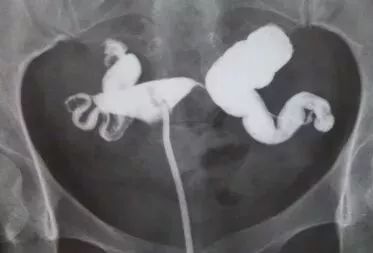

图A 子宫输卵管X片造影提示输卵管积水

图B 四维超声造影提示左侧近端梗阻